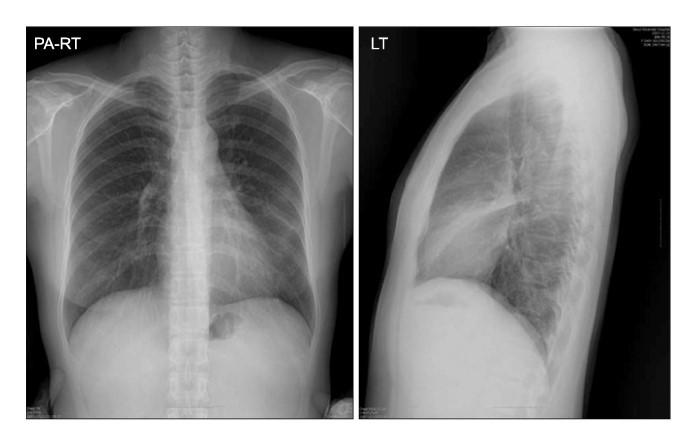

34yo male with cough of 10 days duration

View: PA/lateral

DX: lobar pneumonia - RUL